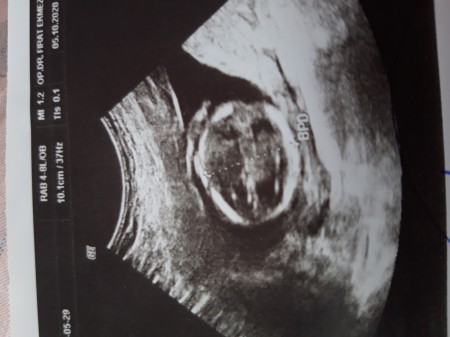

15+0 da kontorle gittim  bebek hareketsizdi doktor 10 dk ya yakin bakti erkek gibi dedi ama hareketsiz oldugu icin bir çikolata ye 30 dk sonra gel tekrar bakayim dedi oyle yaptim 30 dk sonra girdim ulstrasyona baktigi gibi tamam bu erkek dedi kesin mi dedim kesin dedi sizce yanılma pati olurmu sonradan degisirmi cinsiyet

ultrason iyiyse bu haftada kesin belli olur. bizde babası arkadaşlarına gostermek için resim istemişti. doktor yuvarlak içine alıp ilgili bölgeyi çıktı vermişti:)) bu seferki de 1 aya kısmetse belli olur. 11+0 dayız şimdi.

Cinsiyet tahmini